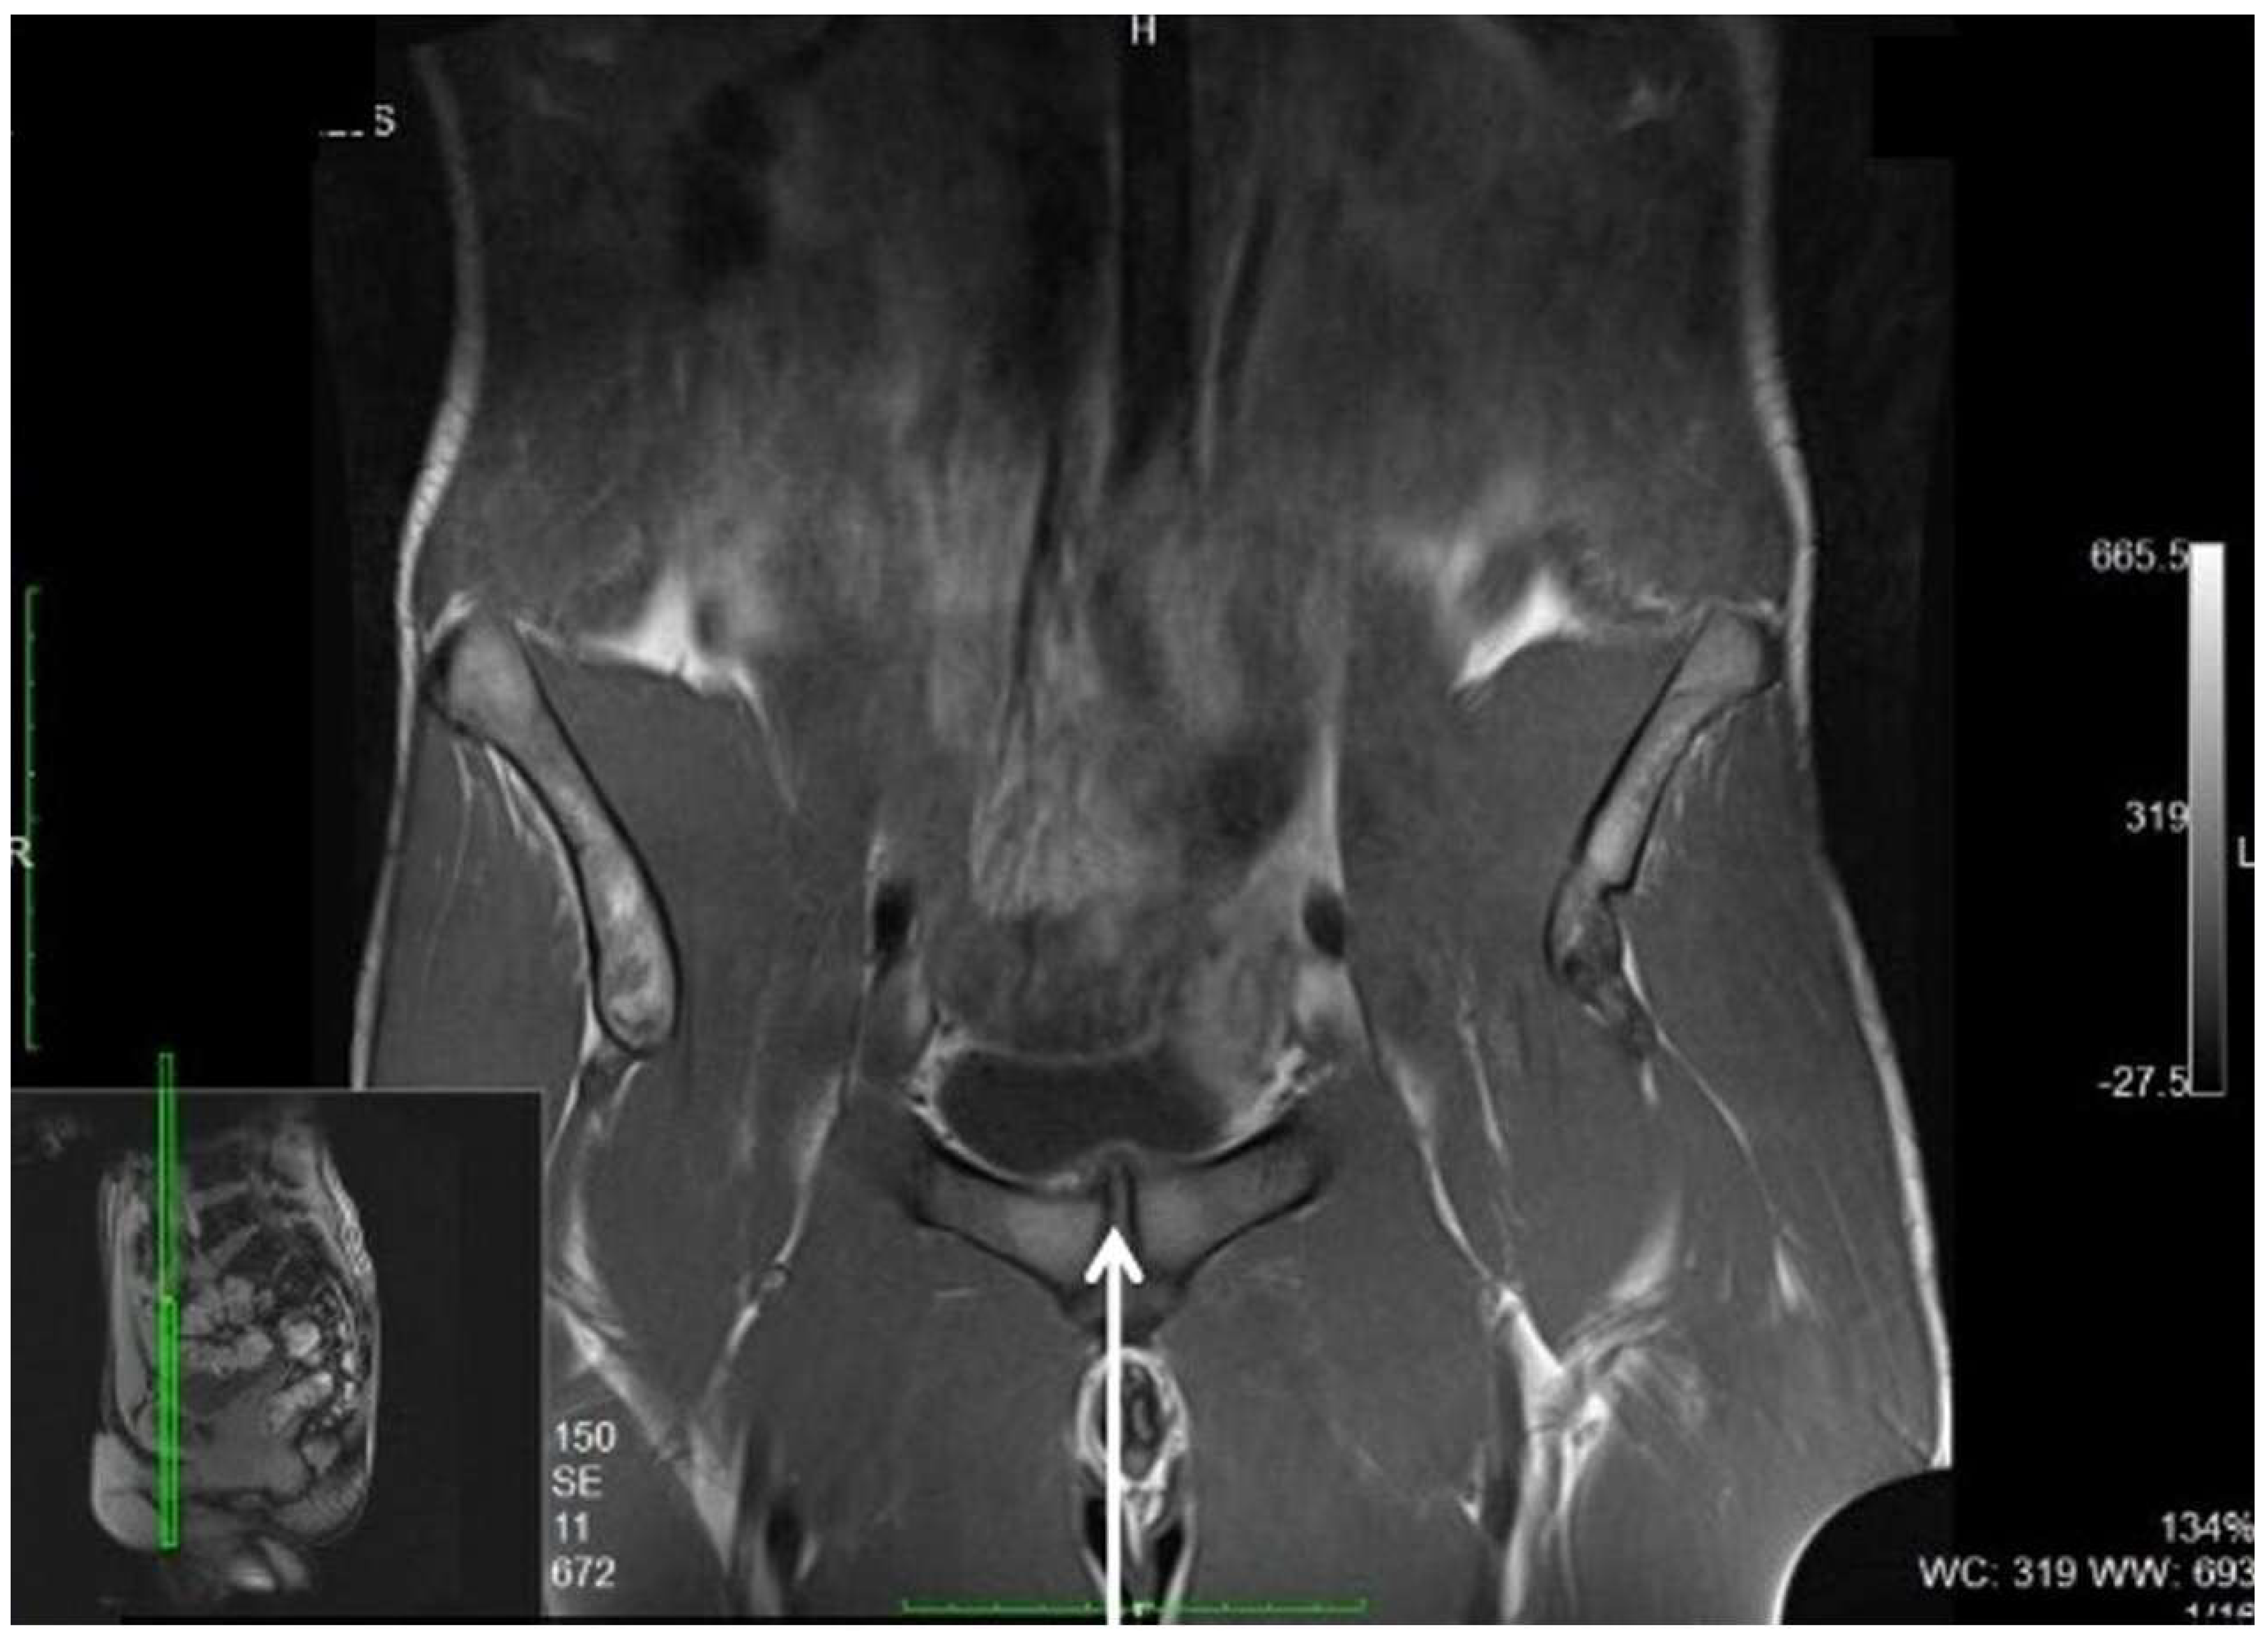

| Bisciotti et al., 2018 [80] | Observational cross-sectional study | IV | 86/90 | lOW | Potential magnetic resonance imaging findings associated with inguinal hernia and inguinal canal posterior wall weakness in athletes |

- Bisciotti, G.N.; Auci, A.; Cena, E.; Corsini, A.; Bisciotti, A.; Zini, R.; Eirale, C.; Parra, F.; Gassaghi, G.; Di Marzo, F.; et al. Potential MRI findings associated with inguinal hernia and inguinal canal posterior wall weakness in athletes. Muscles Ligaments Tendons J. 2018, 8, 290–304. [Google Scholar]